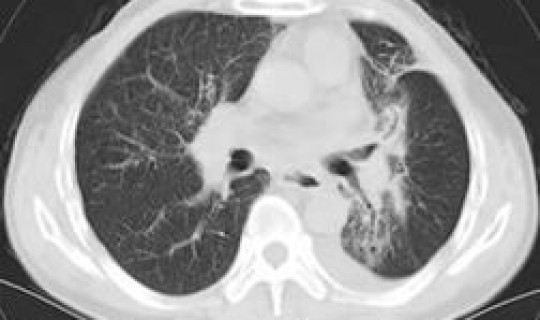

1.史某 ,男,26岁,发病前曾到武汉开会 ,1月22日返回烟台,因咽痛2天,于1月27日到烟台市奇山医院就诊 ,行胸部CT示双肺炎症,收入院治疗。结合患者流行病史,经烟台疾控部门检测,新型冠状病毒核酸检测结果为阳性 。经市级专家组确认该病例为新型冠状病毒肺炎确诊病例。

2.姜某某 ,女,63岁,与确诊病例有密切接触。2月1日因出现无明显诱因干咳到烟台市莱阳中心医院就诊,行胸部CT示双肺炎症 。结合患者流行病史 ,经莱阳中心医院检测,新型冠状病毒核酸检测结果为阳性。采样上报烟台疾控示核酸检测阳性,经市级专家组确认该病例为新型冠状病毒肺炎确诊病例。

3.王某某 ,男,2岁,与确诊病例有密切接触 。2月2日无明显诱因出现发热 ,体温更高达38.1℃,到莱阳中心医院就诊。行胸部CT示双肺纹理增多,收入院治疗。结合患者流行病史,经莱阳中心医院检测 ,新型冠状病毒核酸检测结果为阳性 。采样上报烟台疾控示核酸检测阳性,经市级专家组确认该病例为新型冠状病毒肺炎确诊病例。

4.孙某某,女 ,32岁,与确诊病例有密切接触。2月1日到莱阳中心医院进行排查,行胸部CT示左下肺炎,收入院治疗 。结合患者流行病史 ,经莱阳中心医院检测,新型冠状病毒核酸检测结果为阳性。采样上报烟台疾控示核酸检测阳性,经市级专家组确认该病例为新型冠状病毒肺炎确诊病例。

入院后 ,4例确诊患者在专家组和隔离病房医护团队全力救治和精心护理下,病情持续改善,肺部影像学显示病灶吸收好转 ,各项化验指标均正常,核酸检测均为阴性,经市级专家组评估 ,目前均已治愈,并符合国家第五版新型冠状病毒肺炎确诊病例出院标准。